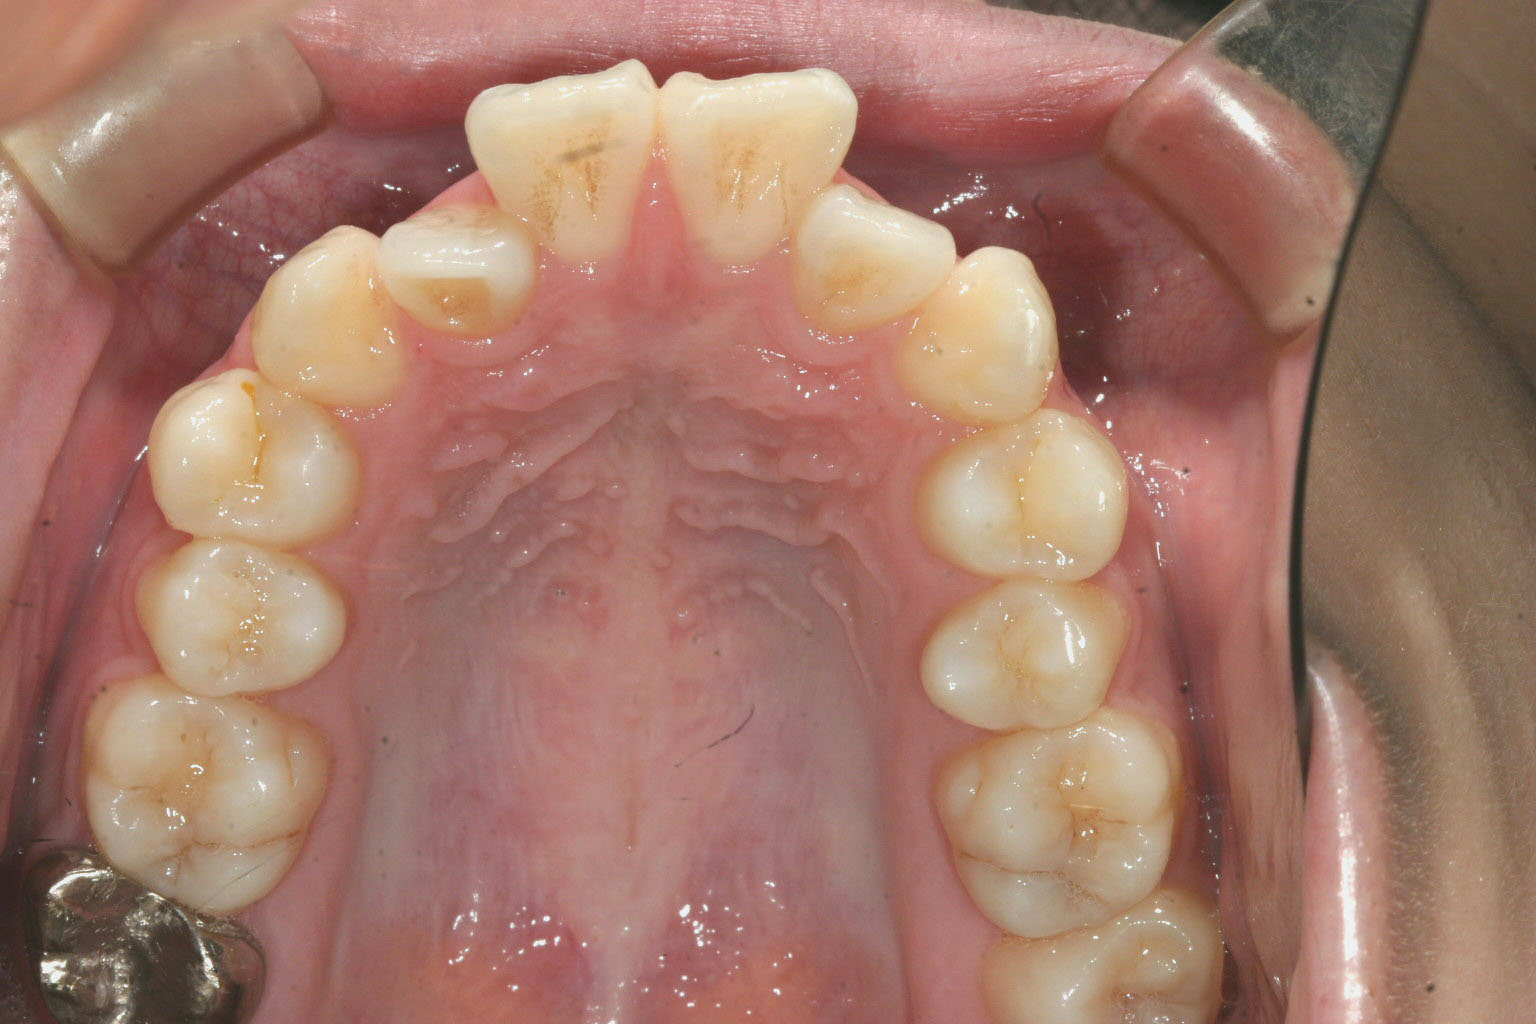

歯列が狭い為にしわ寄せが前歯に現れ、かなりの出っ歯になっています。

下顎もアーチが狭く前歯がガタガタになっています。

前歯の前突が目立ちます。